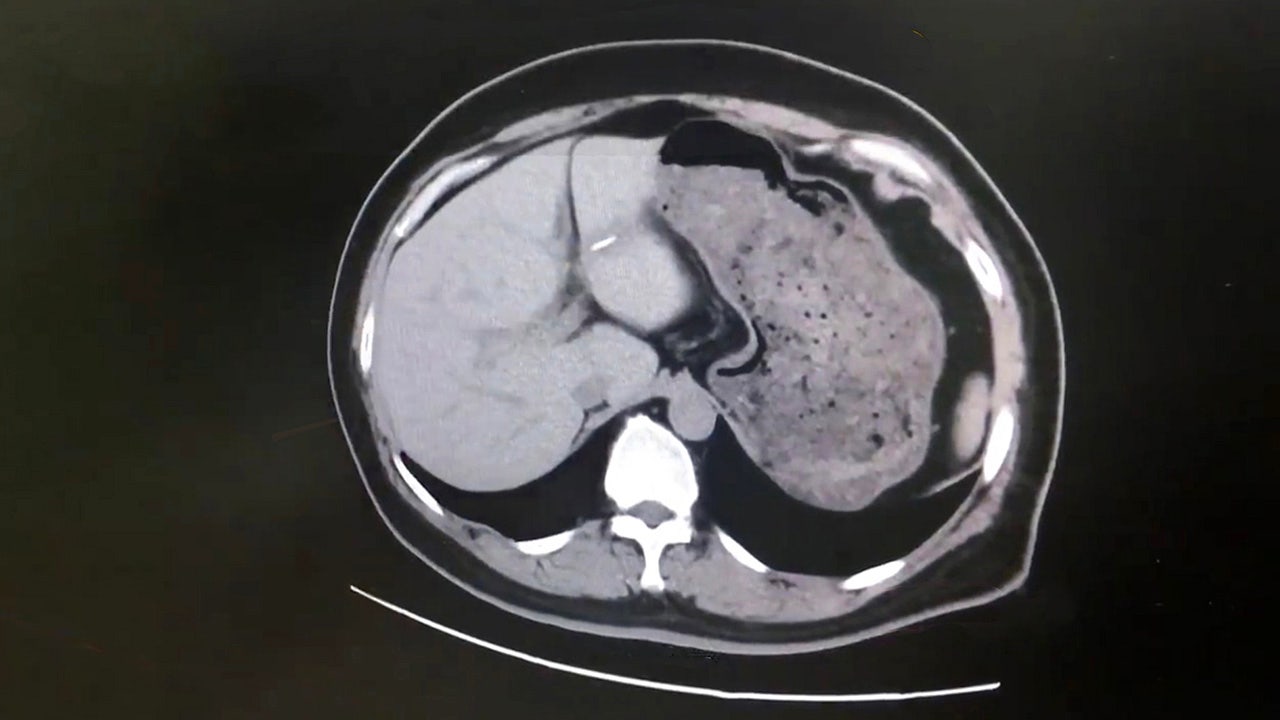

The fish bone was detected after the woman's doctors ordered scans to figure out the root cause of her severe abdominal pains. (AsiaWire)

“While examining her scans, I discovered that the inflammation in her liver was caused by the fish bone,” he told AsiaWire. “After removing the fish bone in microsurgery, her condition has seen some obvious improvement. Because the fish bone was very sharp and could not be digested, it pierced her stomach lining after being swallowed and continued to shift due to the movements of her muscles and was carried by blood vessels into her liver nearby.”